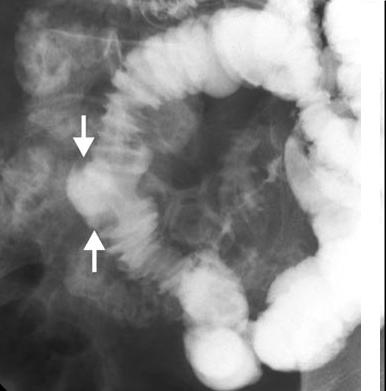

Aspect radiologique TDM de diverticule duodenale

et de l'intestin grele est image d'une contenue a iso-dense

a paroi mince , lisse a hyperdense . A l'intestin image de

air-liquid est frequemment se voyait .

| Deux diverticule du bord

interne de D2 . Image IRM + enteroclyse en coupe

frontale ( coronal ) |

Le meme en TDM

coronale ( fleche rouge ) |